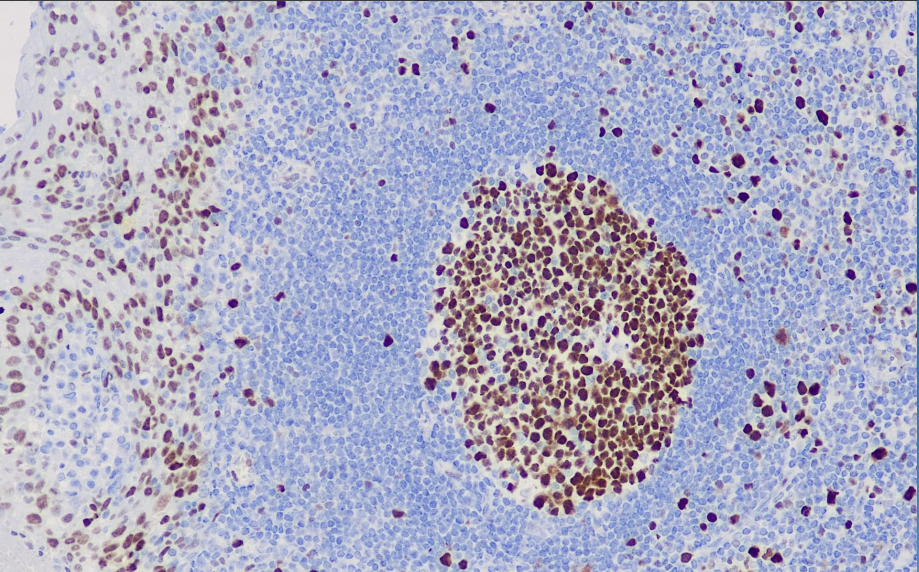

阳性对照: 扁桃体

EZH2抗体试剂可与EZH2分子抗原特异性结合,含EZH2抗体试剂的免疫组化试剂盒适用于滤泡性淋巴瘤、弥漫大B细胞淋巴瘤的精准诊断。